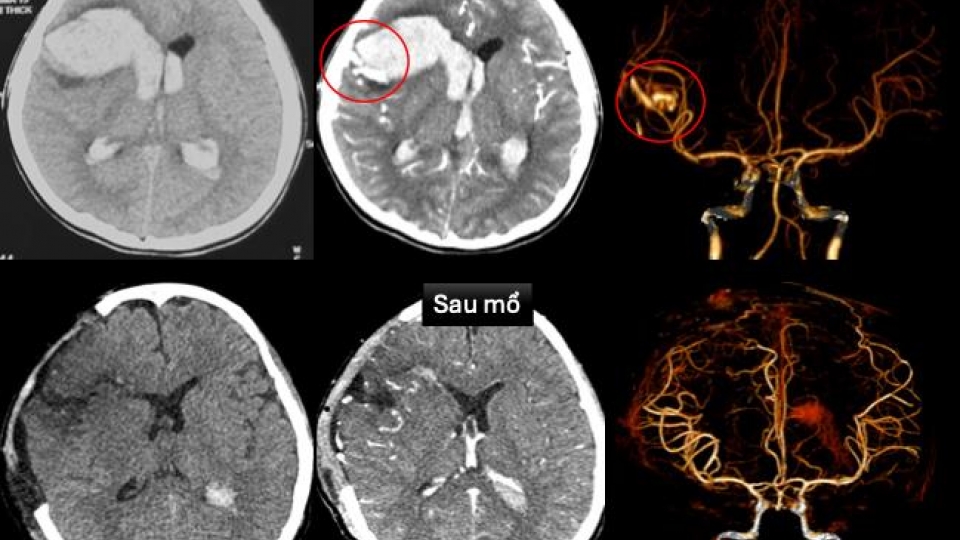

Việc đưa hệ thống mới vào hoạt động giúp bệnh viện mở rộng đáng kể khả năng phát hiện chính xác các tổn thương tim mạch phức tạp mà trước đây khó hoặc không thể chẩn đoán. Nhiều trường hợp bệnh từng bị bỏ sót do hạn chế phương tiện nay đã được phát hiện sớm hơn, tạo điều kiện can thiệp kịp thời, giảm nguy cơ biến chứng và tử vong.

Đáng chú ý, hệ thống thông tim can thiệp hiện đại cho phép áp dụng nhiều kỹ thuật ít xâm lấn, giúp người bệnh tránh phải phẫu thuật lớn.

Theo lãnh đạo Bệnh viện Chợ Rẫy, với người cao tuổi hoặc bệnh nhân có nhiều bệnh nền, phẫu thuật tim tiềm ẩn nguy cơ cao về biến chứng và nhiễm trùng hậu phẫu. Trong khi đó, can thiệp tim mạch qua đường mạch máu giúp quá trình điều trị nhẹ nhàng hơn, an toàn hơn và rút ngắn thời gian hồi phục.